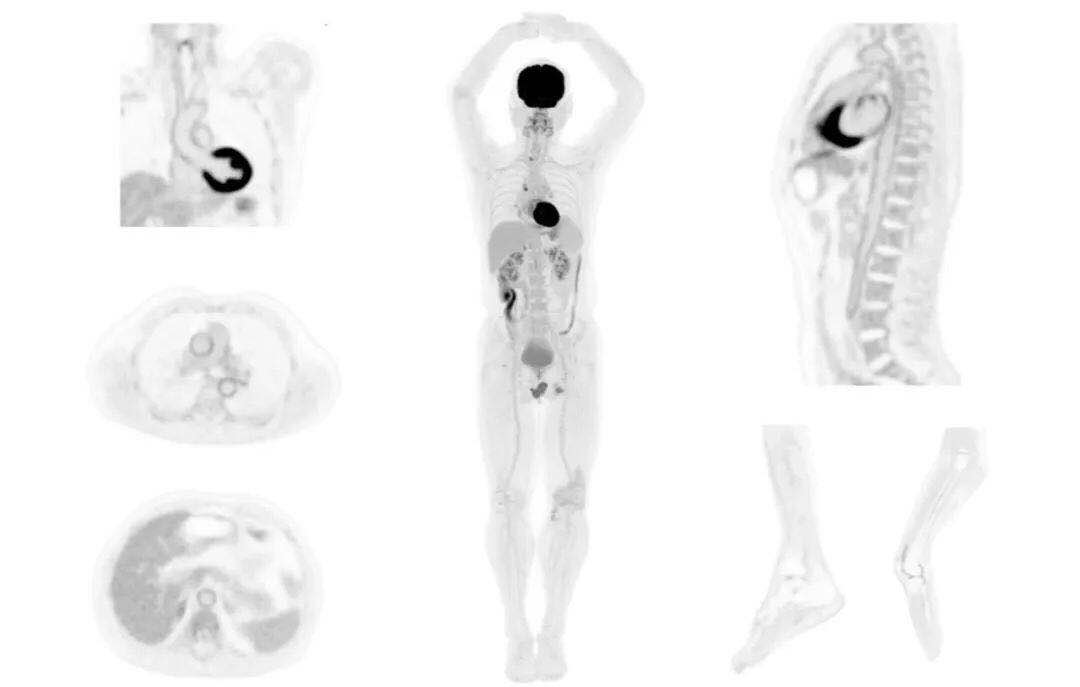

uExplorer探索者不再局限于傳統(tǒng)靜態(tài)代謝過程3D成像,而是在此基礎(chǔ)上新增一個維度——時間,從而實(shí)現(xiàn)4D全景成像。

注射總劑量為7.8mCi,14分鐘全身采集時間,在擁有超高靈敏度與超高分辨率的uEXPLORER上,即可得到展示顯示人體諸多精細(xì)結(jié)構(gòu)的高清三維圖像。

注射總劑量為7.8mCi,注射后1.6小時,基于uEXPLORER探索者掃描1分鐘的圖像

注射總劑量為0.67 mCi FDG(低于常規(guī)劑量的十分之一),基于uEXPLORER探索者掃描15分鐘的圖像

注射總劑量為6.9mCi,注射后10小時,基于uEXPLORER探索者掃描14分鐘的圖像